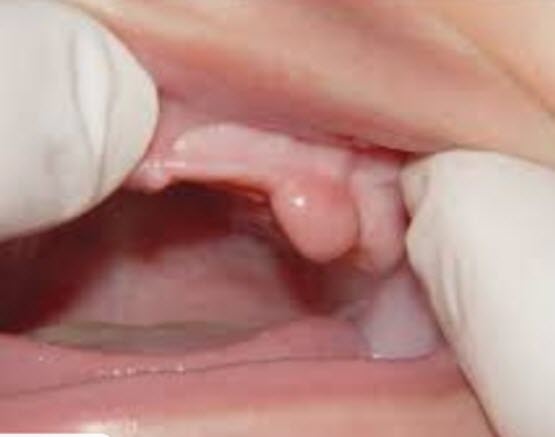

- Ankyloglossia

- 9% present study

- lack of agreement on evaluation/classification

- 11%- Frendenberger et al.

- 1.72% Jorgenson et al.

- 4.4% Friend et al.

- 2.5% Flink et al.

- Photos

- what did they consider as ankyloglossia